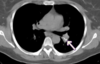

TC ventana pulmonar

Se ven mejor la vía aérea, vasos pulmonares y cisuras, pero todas las estructuras mediastínicas aparecen de un tono gris demasiado similar.